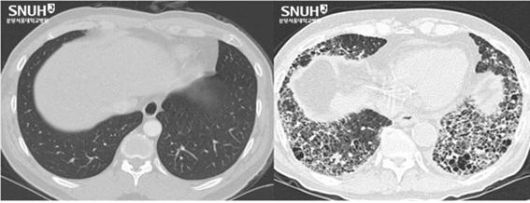

흉부 CT에서 보이는 정상 폐(왼쪽)와 특발성 폐섬유증이 진행해 폐포 사이 간질 조직이 두꺼워지고 벌집 모양을 띠는 섬유화된 폐. 분당서울대병원 제공 |

간질성 폐질환 중 비교적 흔한 병이 특발성 폐섬유증입니다. 특발성이라는 것은 원인을 알 수 없다는 뜻이고, 섬유화가 된다는 것은 양쪽 폐가 서서히 굳어져 딱딱해지는 것을 뜻합니다. 섬유화가 많이 진행되면 폐에 벌집모양의 구멍이 뚫리게 되며 호흡곤란으로 인해 일상생활이 불가능해지고 심하면 사망에 이르기도 합니다.